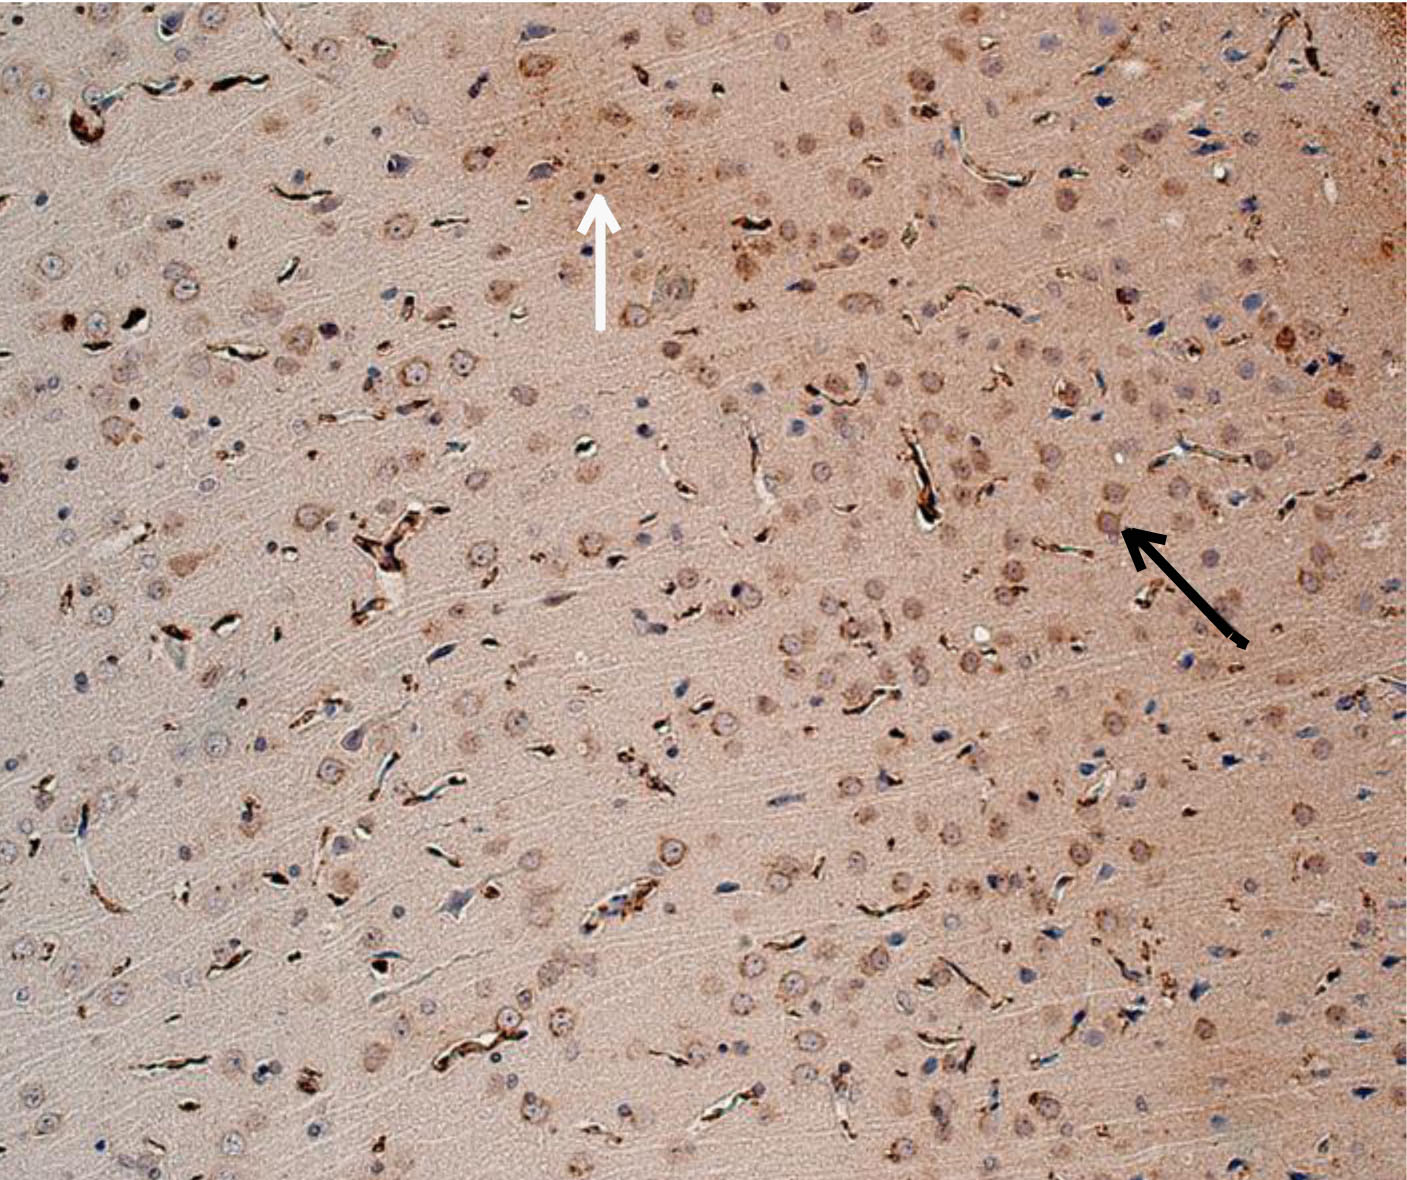

Рис. 3. Животное с СД1 (лечение – аминалон) – от слабой до умеренной экспрессия ИРМ IL-6. Иммуногистохимическое исследование, антитела против IL-6. Увеличение ×200. Черные стрелки – экспрессия в неповрежденных нейронах. Белые стрелки – экспрессия в нейропиле

При оценке результатов ИГХ исследования коры 19-месячных крыс без СД (интактных) была выявлена слабая равномерная экспрессия ИРМ IL-6 во всех слоях первичной и вторичной соматосенсорных областях коры головного мозга. В моторной, а также ретроспленальной коре была обнаружена цитоплазматическая экспрессия IL-6 в перикарионах нейронов от слабой до умеренной степени. У отдельных животных отмечалось наличие умеренной экспрессии IL-6 в базальных отделах коры. Преимущественно экспрессия ИРМ IL-6 определялась в цитоплазме неповрежденных нейронов, реже в нейропиле. В группе животных с экспериментальным СД1 без лечения наблюдалось увеличение выраженности экспрессии ИРМ IL-6 от умеренной до выраженной степени в сравнении с группой 19-месячных животных без СД. Характер экспрессии схож с характером экспрессии у 19-месячных животных без СД. Цитоплазматическая экспрессия ИРМ IL-6 также наблюдалась в моторной и ретроспленальной коре, локализация ИРМ IL-6 определялась в перикарионах нейронах пирамидного, внутреннего зернистого, ганглиозного слоев и в микроглии. В группах фармакокоррекции сукцикардом и аминалоном в сравнении с группой животных с СД1 без лечения наблюдалось снижение выраженности экспрессии во всех областях коры головного мозга, а в базальных отделах вплоть до исчезновения ИРМ IL-6 (рис. 1–4).